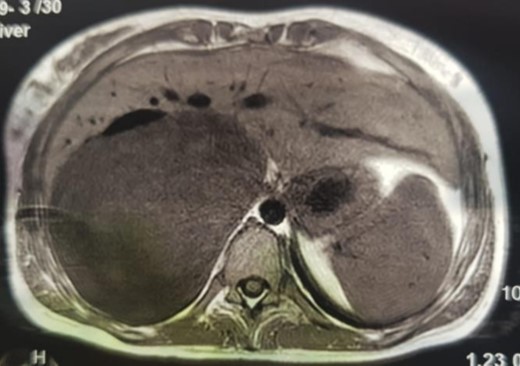

An MRI angiogram to assess the vascular relationships of the tumor revealed a 125 × 110 × 95 mm3 well-bounded, oval, slightly heterogeneous right adrenal mass with a mixed T2 signal and hypointense T1 signal. Angiographic sequences showed no portal venous thrombosis; the lesion was adherent to the right liver and the inferior vena cava (IVC), which was compressed but remained permeable, and came into contact with the superior mesenteric artery and the superior mesenteric vein, which were also permeable. The hepatic pedicle was also slightly pushed forward (Figs. 2 and 3).

MRI, voluminous lesion of the right adrenal medulla in hyposignal T1.